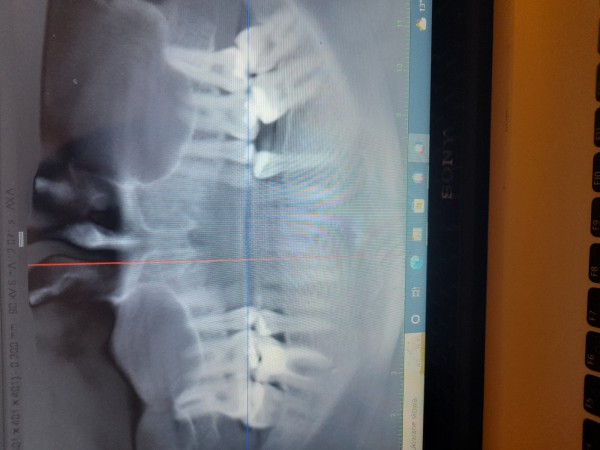

Polipowate zgrubienie śluzówki całej lewej zatoki szczękowej

1 kwietnia wydzlo mi polipowate zgrubienie slozowki calej lewej zatoki szczekowej a w prawej w zachylku zebodolowym 15 mm. Jeden mi powoedzial lekarz ze to wydzielina. Bralam sterydy dwa miesiace i nadal to samo. Boje sie ze jak mam.cala taka lewa zatoke zawalona jakimis zmianami i jakby plynem bo ci lekarze a bylam u kilku nie wiedza czy czasem tam plynu nie ma to wreszcie dostane sepsyalbo czegos gorszego raka lub ze te zmiany zniszcA mi kosci w zatoce. Wysylam zdjecie. Ktos pomoze?